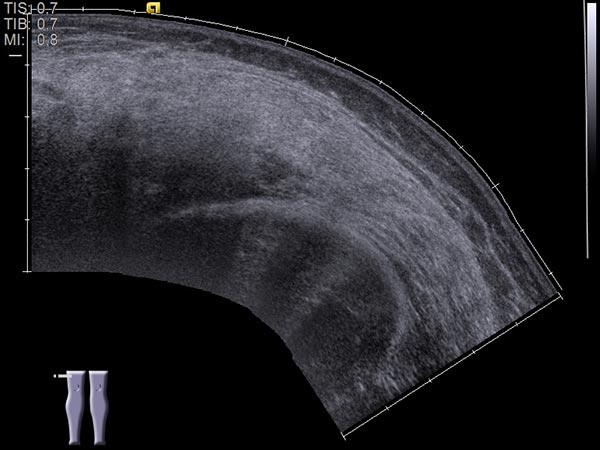

Ultraschallbild (automatisch zusammengesetzte 2D-Darstellung) vor Sklerotherapie. Die hier dargestellten, initial noch echoärmeren Hohlräume der venösen Malformation werden durch die Inflammation, die durch die Sklerosierungstherapie induziert wird, verschlossen werden.

Ultraschallbild (automatisch zusammengesetzte 2D-Darstellung) nach Sklerotherapie. Die echoärmeren Hohlräume der venösen Malformation sind durch die Inflammation, die durch die Sklerosierungstherapie induziert wird, verschlossen. Das Bild erscheint jetzt im Ultraschall homogener und echoreicher. Es können sich somit keine schmerzhaften Thrombophlebitiden mehr abspielen.